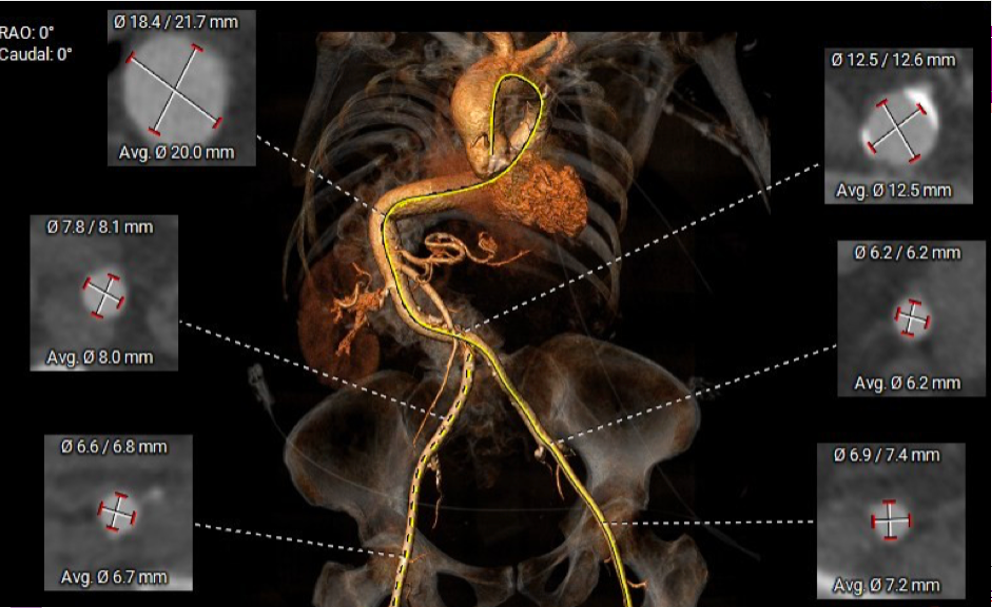

CT-TAVI confirmed Type 1B (RCC-NCC fusion) bicuspid aortic stenosis with severe raphe calcification. Aortic annulus area 486mm2, Area derived diameter 24.9mm. Other CT parameters are as attached. Both iliofemoral arteries diameter and morphology is satisfactory for transfemoral access. However, there is extreme tortuosity of her descending aorta with almost complete S shape but no significant disease or calcification throughout.